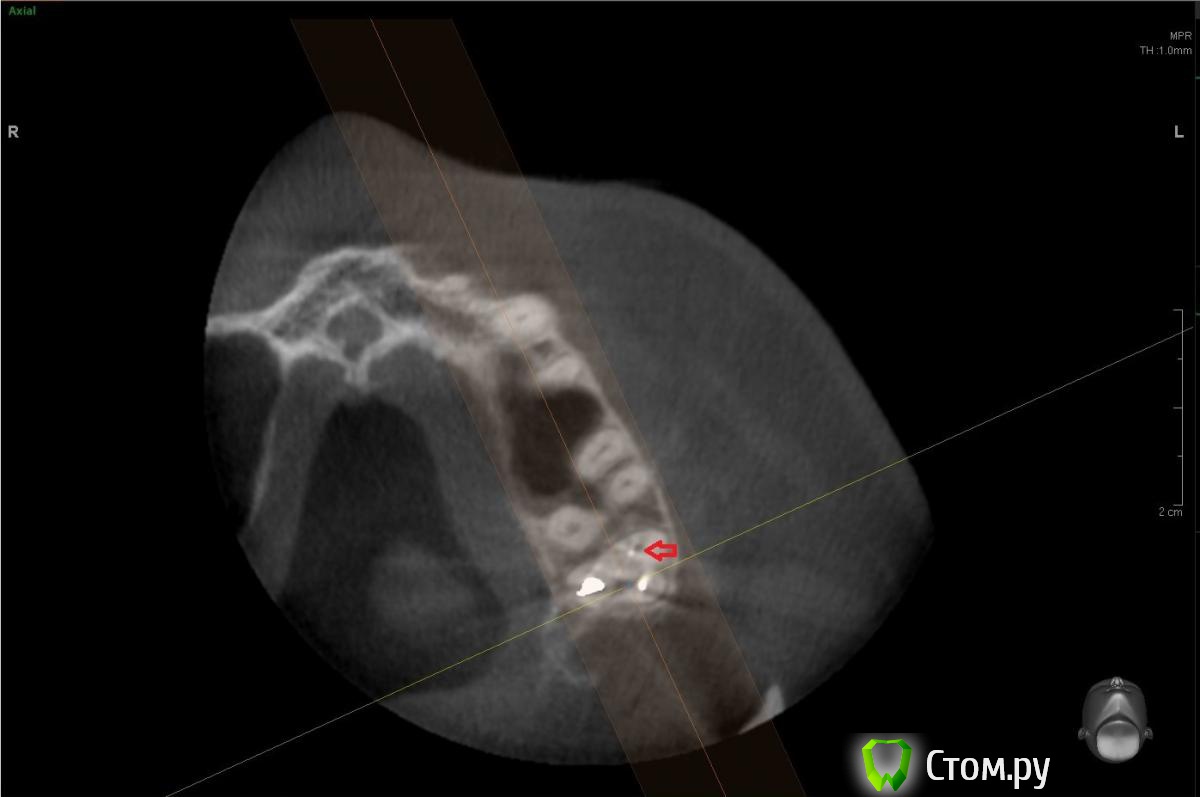

Но оказалось, что это как бы "пора"

post-13796-0-02393600-1400091790.jpg